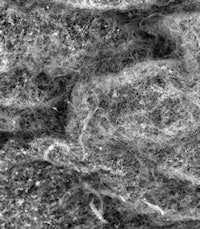

The viscoelastic properties of mucus and saliva are attributed to mucins, large glycoproteins that play a key role in host defense and maintaining a healthy microbiome. Human salivary mucins protect teeth from dental cavities, which are primarily caused by S. mutans colonization.

The research makes a fundamental contribution to scientific understanding of host-microbe interactions, Ribbeck noted. "It is generating a paradigm shift from the textbook view of mucus as a simple catchall filter for particles, toward the understanding that mucus is a sophisticated bioactive material with powerful abilities to manipulate microbial behavior."